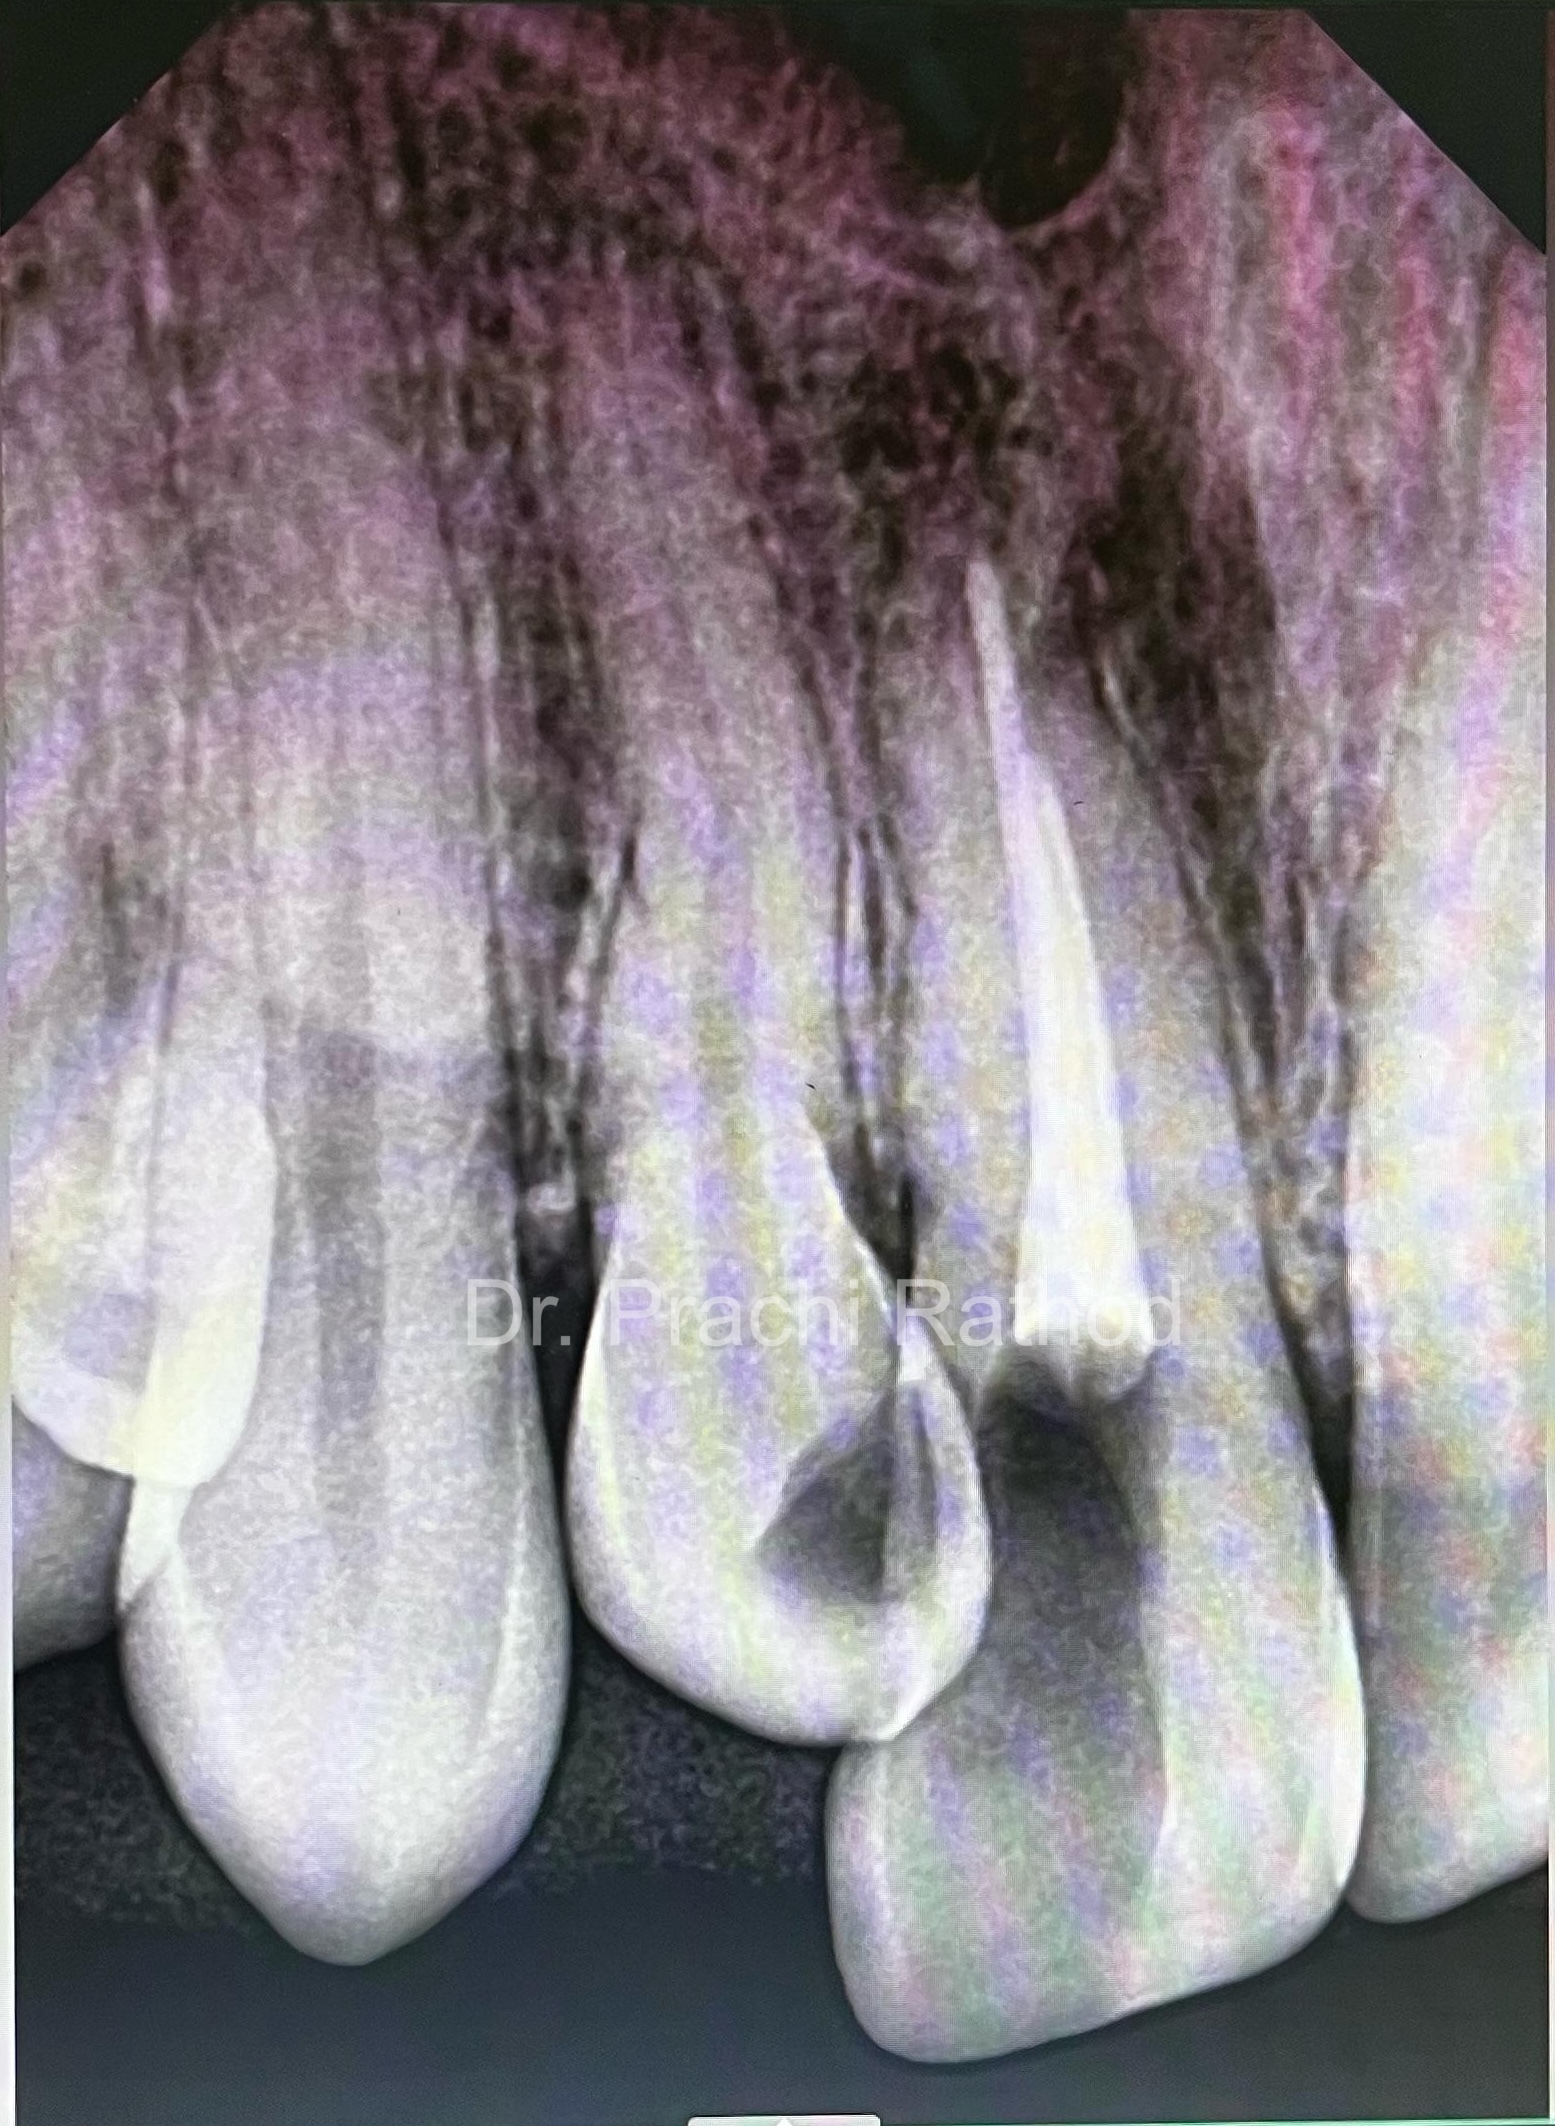

3 month post op RVG